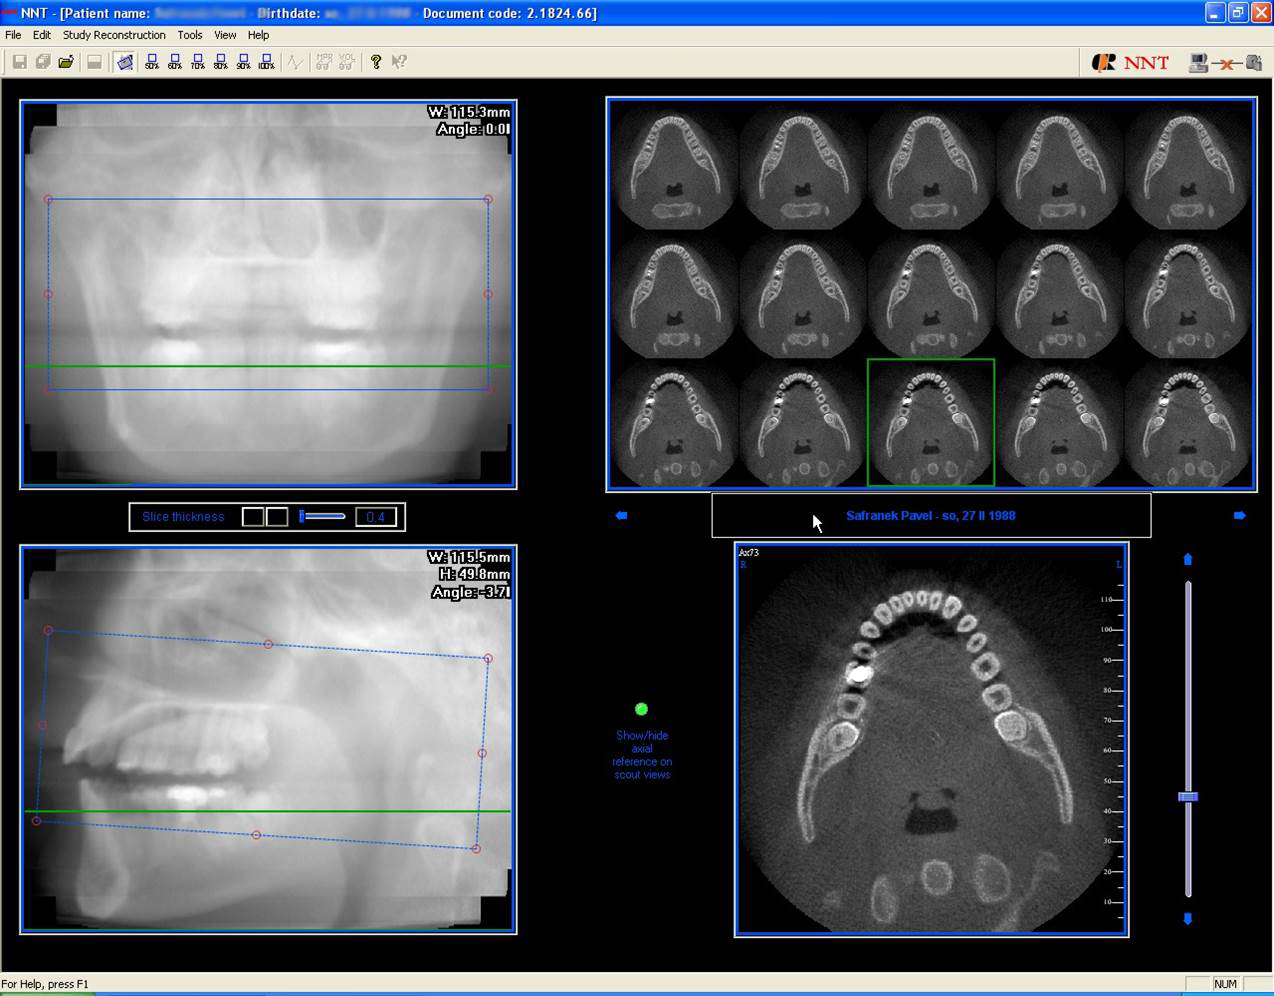

3D DVT - NewTom

Je speciální zubní digitální tříprostorový tomograf (3D), který umožňuje na základě jediného

snímkování vytvořit všechny typy RTG zobrazení, které jsou pro lékaře potřebné. Díky používané technologii tzv. „kuželového paprsku“ a speciálním senzorům je

výrazně zmenšená dávka záření - o více jak 80% proti klasickému CT vyšetření. To je významné zejména u dětí. Pomocí tohoto přístroje je možné zjisti skutečnou situaci v čelistních kostech pacienta tedy množství kosti - můžeme změřit skutečnou šířku i výšku kosti, i kvalitu kosti (hustotu) v místě uvažované implantace. 3D (tříprostorové) zobrazení umožňuje zvýšit prostorovou představu operatéra ještě před vlastní operací a zároveň pacientovi lépe objasnit a ukázat oblast plánovaného zavedení implantátu.

Pacient „neumí číst“ RTG snímky, ale díky 3D zobrazení vidí „svoji skutečnou čelist“

- např. jak je nízká či úzká, vidí průběh nervu nebo velikost čelistní dutiny, což mu umožní i pochopení nutnosti v některých případech provést pomocné zákroky ještě před vlastním zavedením implantátu (viz. kostní štěp, sinus lift, kostní granulát...).

Vyšetření pomocí tohoto přístroje používáme i ve stomatochirurgii (zlomeniny čelistí, zuby moudrosti, cysty, onemocnění čelistního kloubu), ortodoncii (retinované zuby, nadpočetné zuby), parodontologii atd.